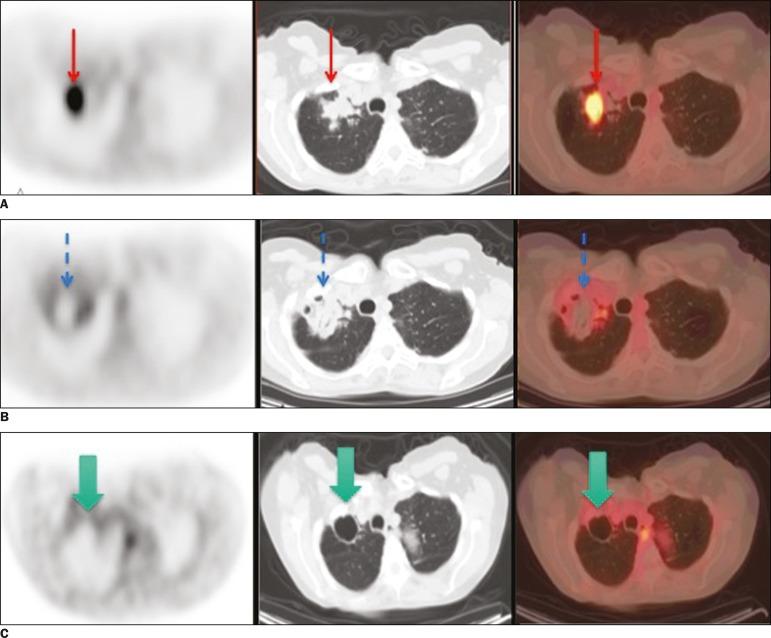

This was a retrospective study of 20 patients (13 males, 7 females; mean age, 65.8 ± 12.1 years) submitted to percutaneous ablation of metastases. All of the lesions treated had shown focal uptake on a F-FDG PET/CT scan obtained at baseline. The primary tumors were mainly colorectal cancer (in 45%) or lung cancer (in 40%). F-FDG PET/CT was performed to identify any residual viable tumor cells. The treatment was considered a success (no viable tumor cells present) if no uptake of F-FDG was noted on the F-FDG PET/CT scan.

Twenty-six lesions were submitted to percutaneous ablation with either cryoablation (n = 7) or radiofrequency ablation (n = 19). The mean lesion diameter was 2.52 ± 1.49 cm. For the detection of viable tumor cells, F-FDG PET/CT had a sensitivity, specificity, accuracy, positive predictive value, and negative predictive value of 66.7%, 95%, 88.5%, 80%, and 90.5%, respectively. There was a significant correlation between the F-FDG PET/CT findings and the results of the follow-up studies (kappa = 0.66; < 0.01).

材料与方法

这是一项对20例接受经皮转移灶消融术患者(13例男性,7例女性;平均年龄65.8±12.1岁)的回顾性研究。所有接受治疗的病灶在基线时的F-FDG PET/CT扫描中均显示局灶性摄取。原发肿瘤主要为结直肠癌(45%)或肺癌(40%)。进行F-FDG PET/CT以识别任何残留的存活肿瘤细胞。如果在F-FDG PET/CT扫描中未发现F-FDG摄取,则认为治疗成功(无存活肿瘤细胞)。

结果

26个病灶接受了冷冻消融(n = 7)或射频消融(n = 19)的经皮消融。病灶平均直径为2.52±1.49 cm。对于存活肿瘤细胞的检测,F-FDG PET/CT的敏感性、特异性、准确性、阳性预测值和阴性预测值分别为66.7%、95%、88.5%、80%和90.5%。F-FDG PET/CT结果与随访研究结果之间存在显著相关性(kappa = 0.66;P < 0.01)。